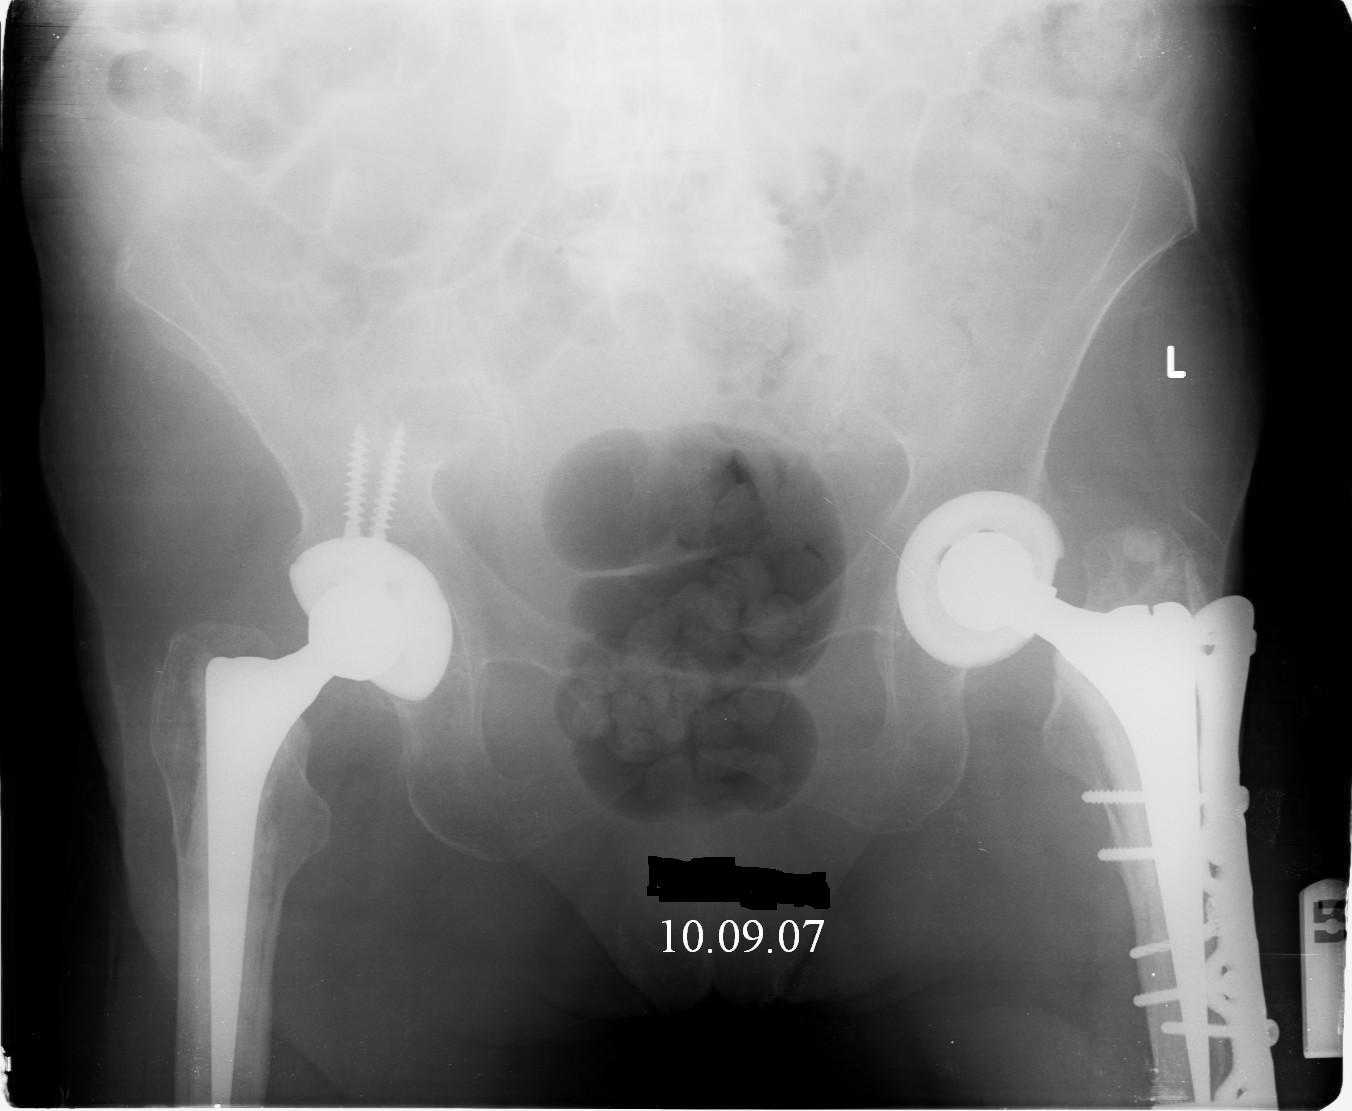

Great case Alex

Reminded me of a case I did a couple years ago - 30 year old woman with juvenile rheumatoid arthritis and a nonunion below her stem. Fixed with retrograde nail which docked with the stem and a lateral locking plate. Image attached. One of the companies should come up with a stem design and nail system that anticipates this need.